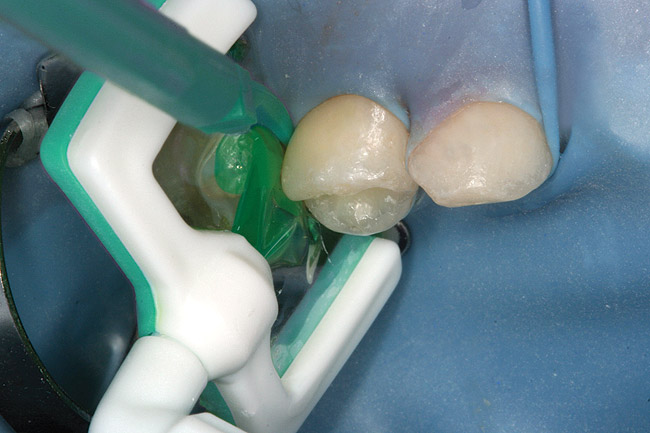

Figure 7  Matrix in place showing extrusion of hydrochloric acid.

Figure 7

Caries infiltration is a simple, straightforward technique. Before treatment, the tooth should be thoroughly cleaned and isolated with a rubber dam (Figure 5 and Figure 6). Treatment kits contain all of the materials required for the technique (except the rubber dam), including specially designed proximal tips that are used for accurate delivery of the acid etch and infiltrant resin during the procedure. These carriers consist of an ultrathin film perforated on one side for direct placement at the treatment site, which protects adjacent teeth. The tips swivel 360°, allowing application from different angles. All syringes contained in the kit are screw-type applicators, which ensure controlled extrusion of the materials.

Specially designed dental wedges are inserted to slightly separate the carious tooth from adjacent teeth. A 15% hydrochloric gel is used to remove the "pseudointact" surface and open the pore system of the incipient lesion body (Figure 7).85 After rinsing (Figure 8), the area is dried with ethanol (Figure 9), followed by dry air. Then, the infiltrant is applied and allowed to penetrate the lesion pores by capillary action for 3 minutes (Figure 10). Any excess material is removed with dental floss, and the infiltrant is light cured from three angles for 40 seconds (Figure 11). A second layer of infiltrant is applied for 1 minute, and light cured for 40 seconds (Figure 12).86 It should be noted that the infiltrant is not radiopaque because fillers would affect the viscosity. Efficacy of the treatment can be tracked at future visits by lack of lesion progression.